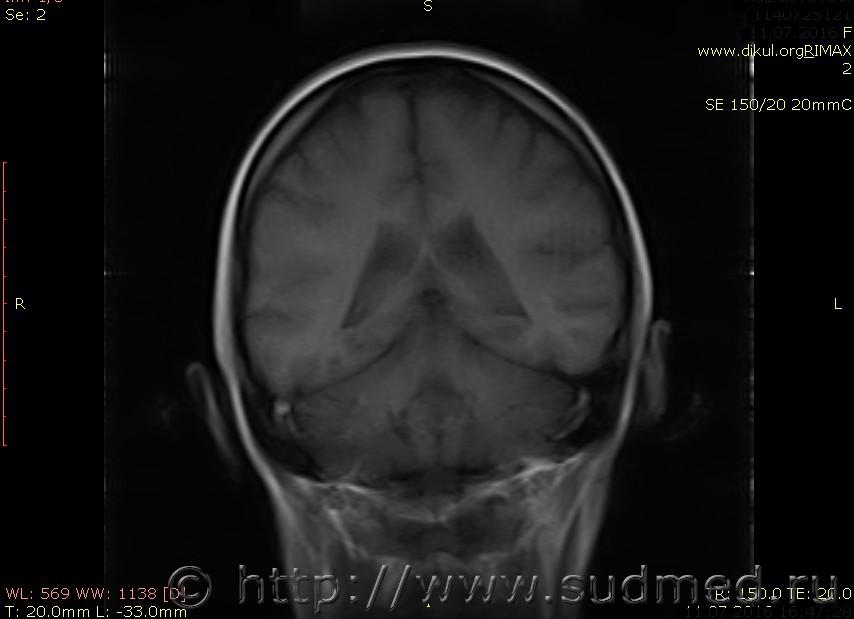

МРТ головного мозга показало: МР-данных за наличие очаговых изменений в веществе головного мозга на момент исследования не выявлено. МР-признаки нарушения соотношения в атланто-осевом суставе. Определяется ассиметрия положения зубовидного отростка С2 относительно боковых масс С1(справа 6,5; слева 4 мм.)

Сама по себе эта информация даёт основания подозревать вывих первого шейного позвонка, но однозначно не свидетельствует о наличии вывиха. Нужно смотреть на снимках наличие реакции со стороны мягких тканей, в т.ч. связочного аппарата, нужно анализировать особенности неврологической патологии, её динамику и проч.

Запрошен электронный вариант снимков из учреждения, где делалось МРТ. Т.к. с самого снимка делать копии не получается,очень мелкие кадры. Завтра попробую вставить в сообщение. (Но СМЭ снимок не смотрел, смотрел только мед.карту, в которой находилось описание МРТ).

Посмотрите пожалуйста снимки, надеюсь на них видны позвонки С1,С2?

Прошу прощения, попробую снова прикрепить файлы. Данные учреждения и пациента убраны.